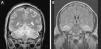

The patient was a 38-year-old man with a medical history hypothyroidism treated with thyroid hormone replacement therapy. He also presented personality disorder and had attempted suicide several times. He was found unconscious inside a car inhaling exhaust gases, and beside him were 2 empty blister packs of benzodiazepines. Upon arrival at the emergency department, the patient had a low level of consciousness (Glasgow Coma Scale=3) and mid-dilated miotic pupils which were poorly reactive; as a result, he underwent orotracheal intubation. A cranial CT (Fig. 1) revealed diffuse hypodensities in both cerebellar hemispheres, basal temporal white matter bilaterally, both internal capsules, and the globus pallidus. The patient was admitted to the intensive care unit (ICU). A urine toxicology test revealed benzodiazepine and methadone, while CO-oximetry showed carboxyhaemoglobin levels of 23.6%. The patient was therefore mechanically ventilated with 100% oxygen until his carboxyhaemoglobin levels decreased to 0.9%, approximately 6hours later. In the 48hours after being admitted to the ICU, the patient's neurological symptoms improved to the point where he was able to obey simple instructions, although he remained drowsy. However, 72hours after admission to the ICU, the patient's state of consciousness deteriorated suddenly. An additional cranial CT (Fig. 1) revealed severe hydrocephalus affecting the lateral ventricles and third ventricle, resulting in a significant mass effect. The patient underwent emergency surgery: first, an external ventricular drain was put in place, from which exuded a clear liquid under high pressure, and then, a decompressive craniectomy of the posterior fossa was performed to relieve cerebellar herniation. After surgery, the patient remained in coma for the next 5 days (flexion–extension of both upper limbs was the only response to painful stimuli). A follow-up cranial MRI scan performed 4 days after surgery (Fig. 2) showed multiple cerebral infarcts in an early subacute stage, extensively affecting the limbic system, hippocampus, fornix, and basal temporal area bilaterally. Patchy areas of small bilateral cortical infarcts could also be observed in the frontal and parietal lobes, as well as extensive infarcts in both cerebellar hemispheres, with the most damage occurring in the territory of the superior and anterior inferior cerebellar arteries; no signs of hydrocephalus were seen. Taken as a whole, these findings suggest multiple anoxic-ischaemic encephalic lesions secondary to CO poisoning. As of the fifth day after surgery, our patient's neurological symptoms had improved progressively, reaching an adequate level of consciousness and showing no focal neurological signs. Three days later, hydrocephalus resolved and the external ventricular drain was removed after remaining closed for 48hours without visible neurological deterioration.

(A) Diffuse hypodensity in both cerebellar hemispheres, basal temporal white matter bilaterally, both internal capsules, and the globus pallidus. (B) Severe dilation of the lateral ventricles and third ventricle (the fourth ventricle was normal), which results in severe mass effect leading to effacement of the convexity sulci and a decrease in the size of the basal cisterns.